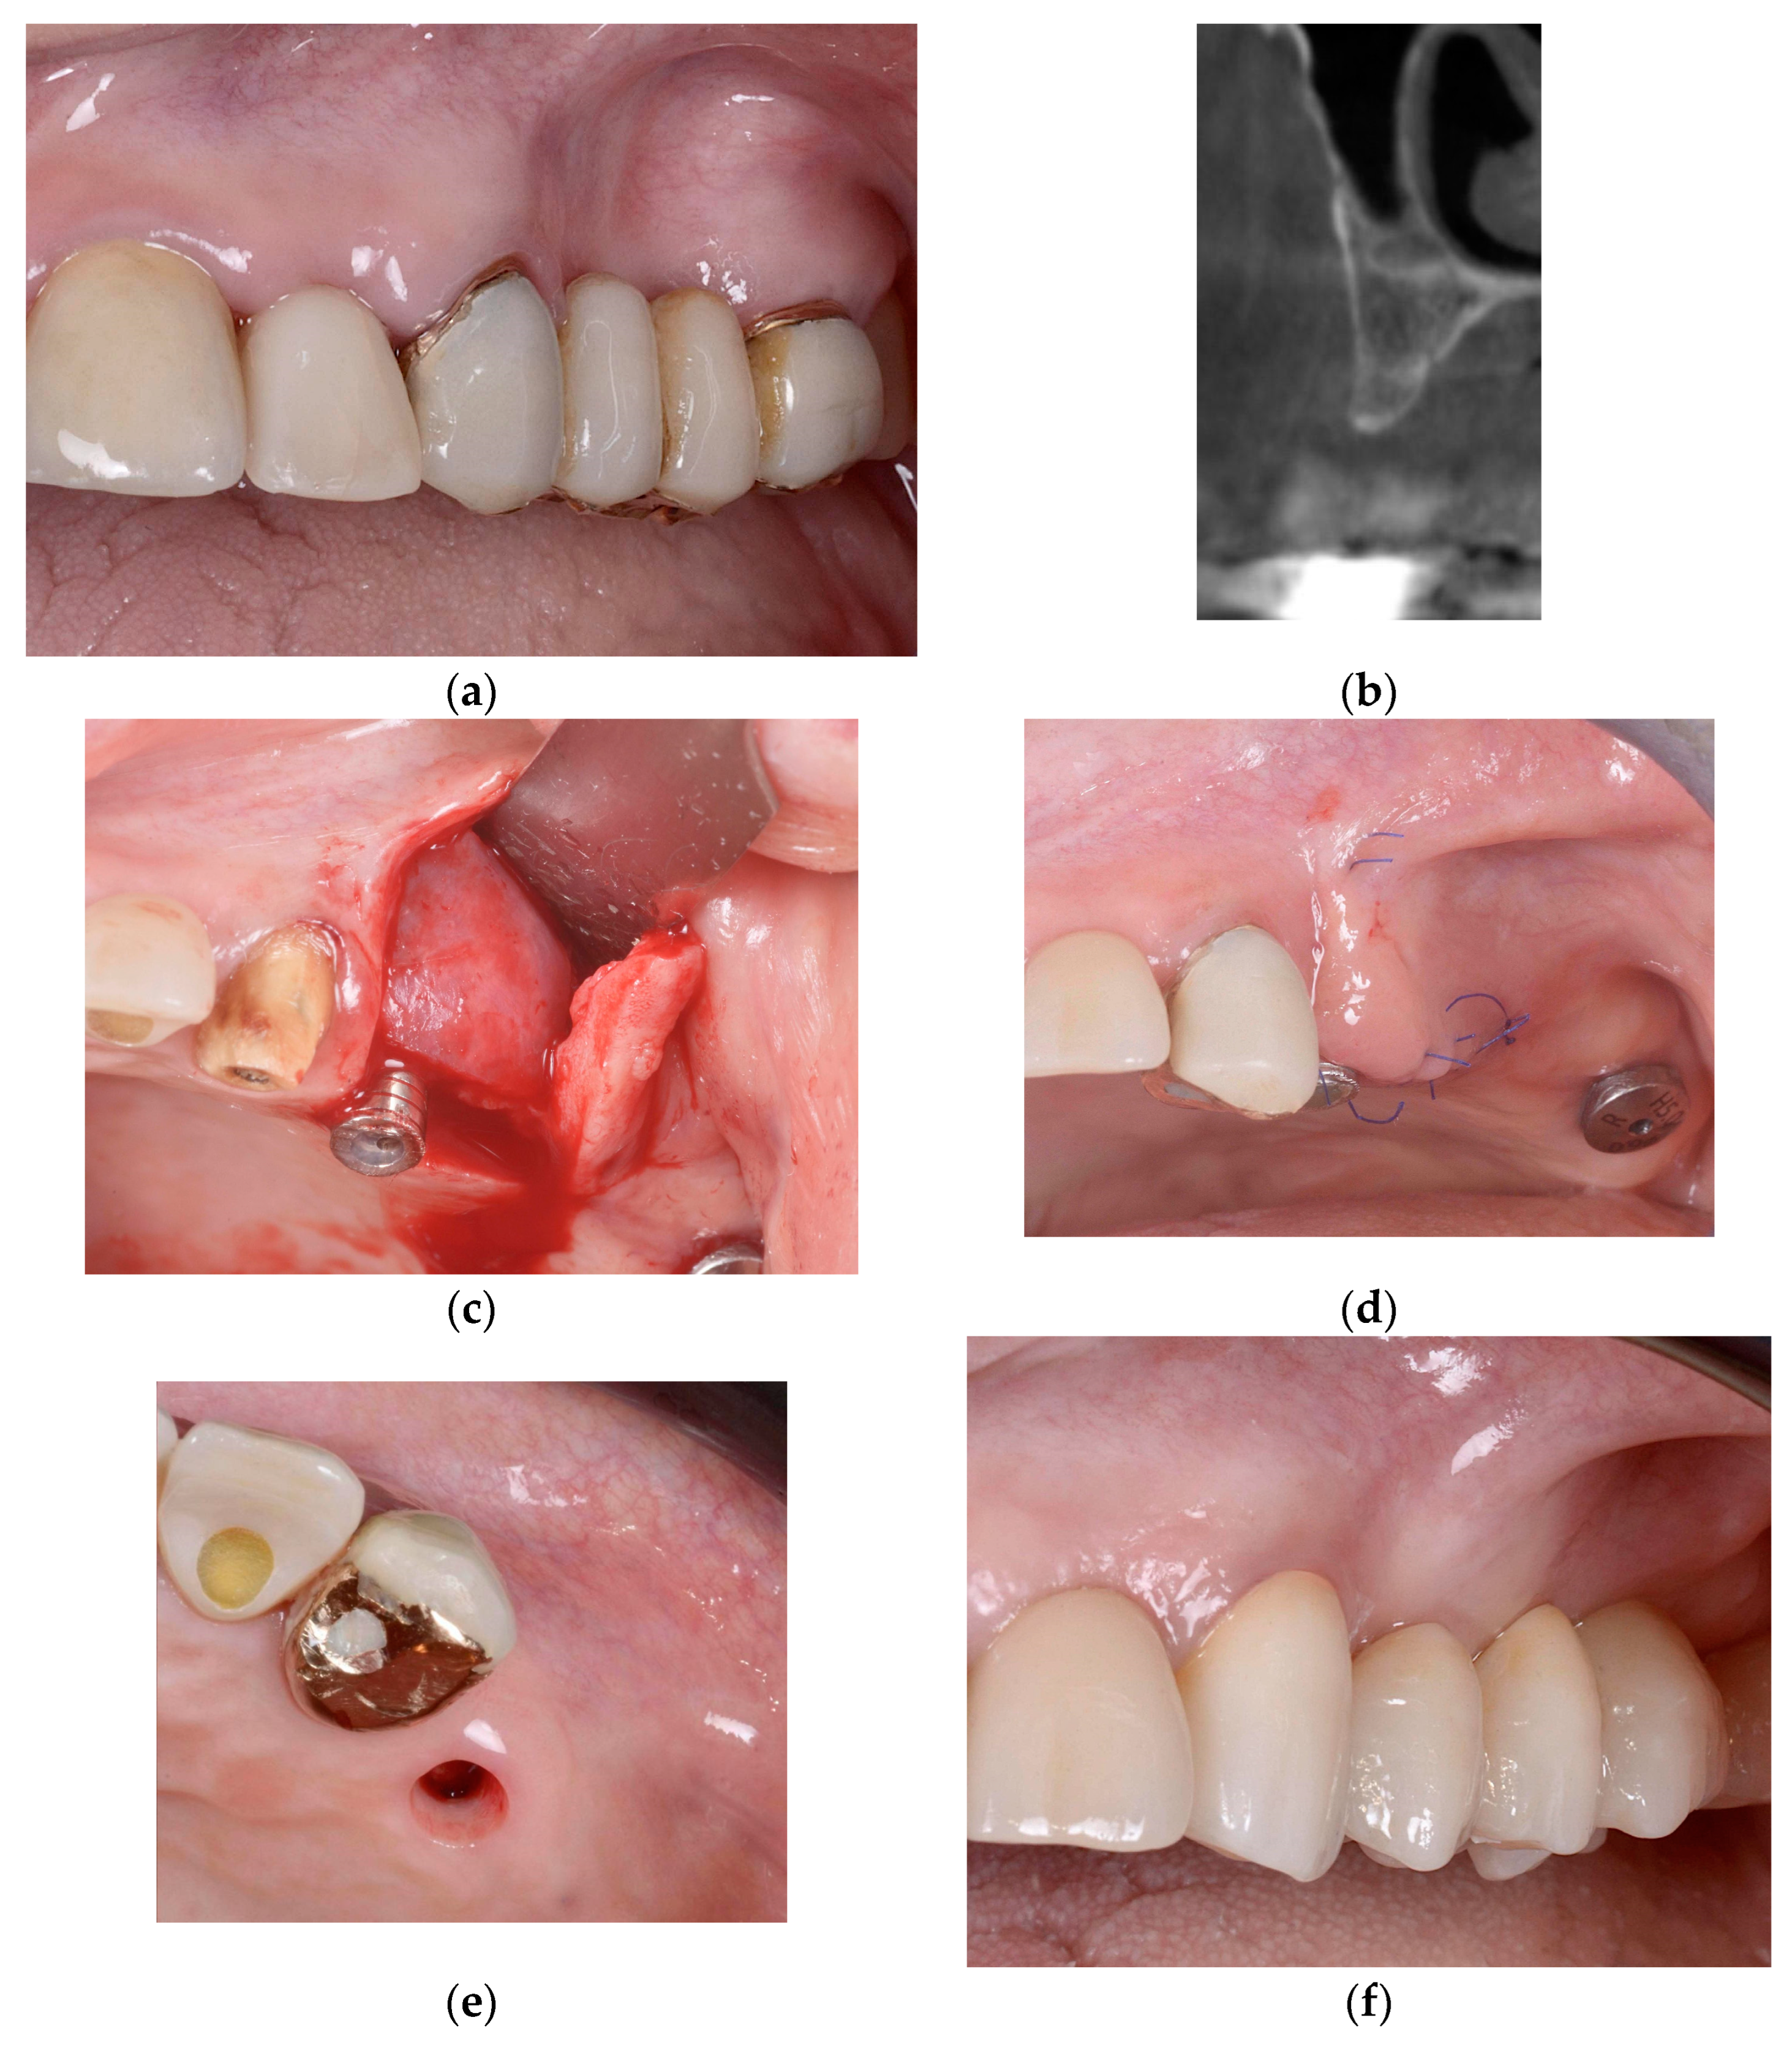

2.2.1. Horizontal and Vertical GBR Using F.I.R.S.T.

2.2.2. Immediate Implant Placement Using F.I.R.S.T.

2.2.3. ARP and Delayed Implant Placement Using F.I.R.S.T.

- Foti, V.; Rossi, R. Fibrinogen-induced regeneration sealing technique (first) an improvement and modification of traditional gbr: A report of two cases. Mod. Res. Dent. 2020, 5, 476–485. [Google Scholar]

- Foti, V.; Savio, D.; Rossi, R. One-time cortical lamina: A new technique for horizontal ridge augmentation. A Case Ser. Br. J. Healthc. Med. Res. 2021, 8, 22–30. [Google Scholar] [CrossRef]

- Foti, V. Fibrinogen-induced regeneration sealing technique (f.I.R.S.T.). In Building Better Bone: A Comprehensive Guide to gbr Techniques; Rossi, R., Ed.; Quintessence Publishing: Batavia, IL, USA, 2024; pp. 210–227. [Google Scholar]

- Faro, L.L.; Strappa, E.M.; Carù, F.G.; Nanni, M.; Invernizzi, M.; Testori, T. Rigenerazione ossea guidata con tecnica first (fibrin-induced regeneration sealing technique). Case report con evidenze istologiche. Quintessenza Internazionale Riv. Di Odontoiatr. 2023, 37, 10–21. [Google Scholar]